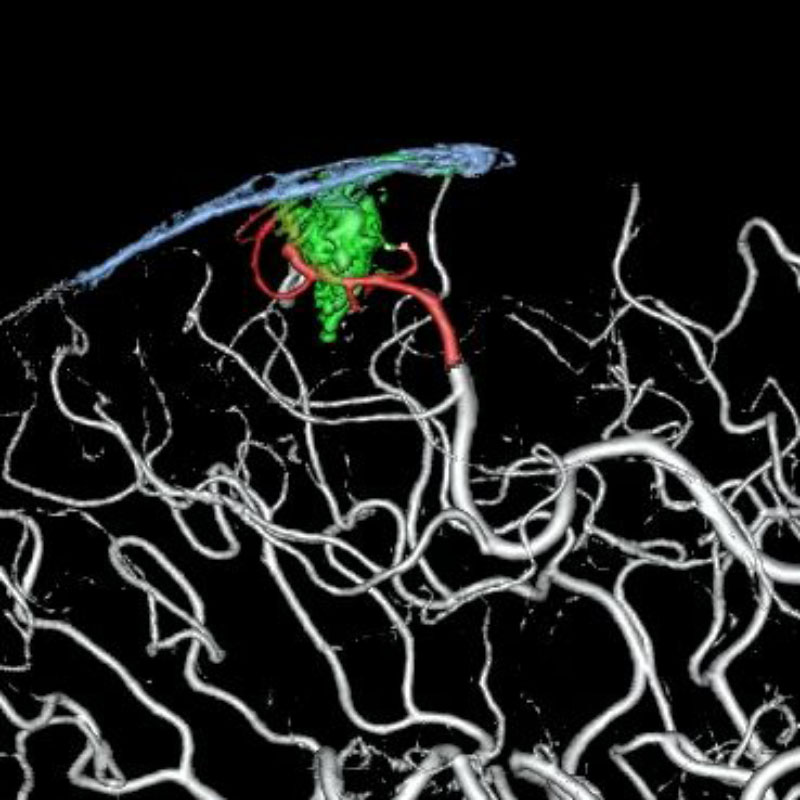

脳動静脈奇形

摘出術

松田/矢田